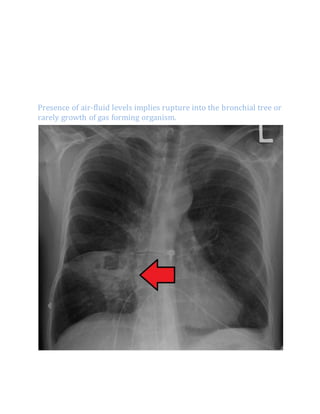

x-ray:-

Radiographic abnormality may start with a pneumonic infiltrate

followed by the development of one or more spherical areas of more

homogeneous density in which air-fluid levels often arise indicating the

formation of a bronchial communication.

Presence of air-fluid levels implies rupture into the bronchial tree or

rarely growth of gas forming organism.

Pulmonary abscess on CXR